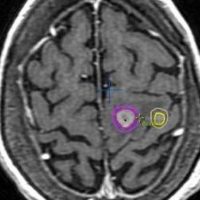

定位放射線治療のイメージ:ピンポイントとはいえない

近接する2つの転移巣への定位放射線治療です。右側は放射線治療計画の等線量曲線といいます。5回に分けて25グレイの放射線治療を行います。

転移性脳腫瘍は,画像で見えているところよりも少し周囲の脳へ浸潤しています。ですからガンマナイフでもサイバーナイフでもリニアックでも,見えている腫瘍 GTVよりも,PTVがやや広めになります。どういうことかというと,脳転移にピンポイントで放射線をかけるというのは,ある意味では「ウソ」で,周囲の脳は必ず被曝します。ガンマナイフでもサイバーナイフでも同じことです。